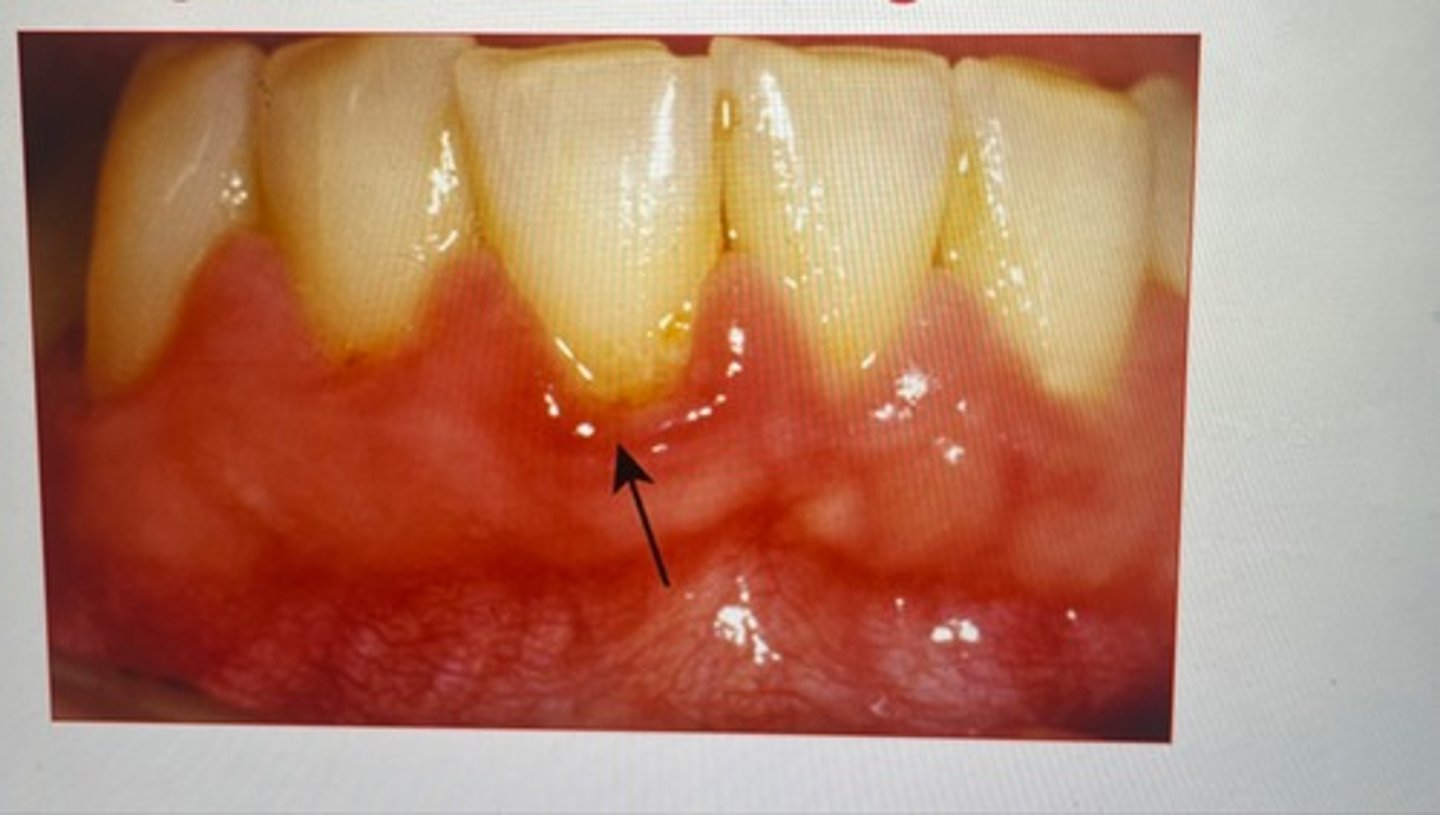

Method/technique: Bristles are directed apically at 45 degrees (up for maxillary and down for mandibular) to long axis of tooth, mostly it is difficult to place at 45 degrees so placing parallel to teeth is also beneficial

Now press the bristles slightly so that they enter the gingival sulcus and embrasures.

Vibrate the brush back and forth with short strokes for 10-15 strokes for each position and move to the next teeth